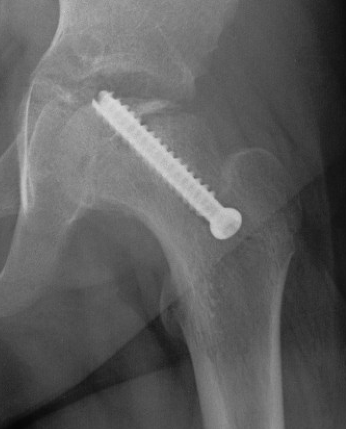

Subtrochanteric fracture

Subtrochanteric fracture likely causes by multiple drill holes / attempts

Cause

Too low screw entry

Multiple drill holes to get correct entry

Management

Intramedullary nail